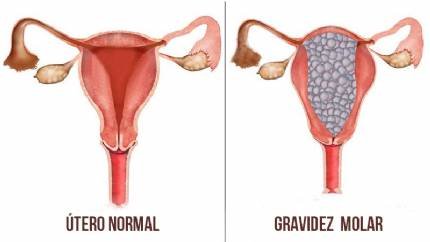

Em outros casos, uma anormalidade cromossômica pode levar a uma condição rara chamada gravidez molar, na qual os tecidos que deveriam formar um feto tornam-se um crescimento anormal no útero.

Existem dois tipos de gravidez molar:

- Uma gravidez molar completa é causada quando o óvulo não possui informação genética. Desenvolve uma placenta que se parece com um cacho de uvas sem um feto acompanhante.

- Uma gravidez molar parcial ocorre quando um óvulo é fertilizado por dois espermatozoides. Causa o desenvolvimento de um embrião gravemente mal formado e geralmente não sobrevive.